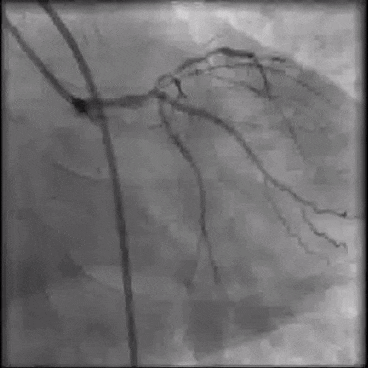

Рука после коронографии

Рука после коронографии 111 фотографий